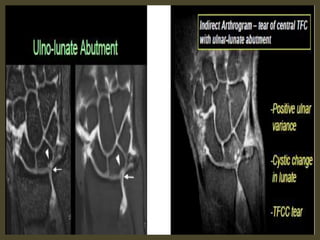

Ulnar variance may be :

Neutral (both the ulnar and radial articular surfaces at the same

level)

Positive (ulna projects more distally)

Negative (ulna projects more proximally)

Causes

trauma or mechanical

distal radius/ulnar fractures with shortening (e.g. impaction) &

angulation

DRUJ ligamentous injuries (e.g. Galeazzi & Essex-Lopresti)

surgical shortening of ulna or radius

growth arrest (e.g. previous Salter-Harris fracture)

Congenital

Madelung deformity/reverse Madelung deformity

Associations

positive ulnar variance is associated with ulnar impaction syndrome.

negative ulnar variance is associated with Keinbock,s disease and ulnar

impingement syndrome

Positive ulnar variance secondary to TFC tear.

TFCC 1B tear (arrow) on coronal T1-WI (B) and coronal FS T2-WI (C).

Negative ulnar variance secondary to TFC tear.

Negative ulnar variance.